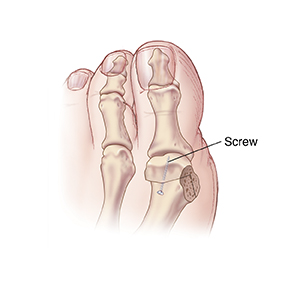

Head chevron osteotomy

The first metatarsal bone is cut. Its head is moved closer to the second metatarsal bone. A screw or pin can be used to hold the first metatarsal bone in position. The bony bump is also removed. You will need to wear a surgical shoe or boot for a few weeks. This is to protect your foot while healing.